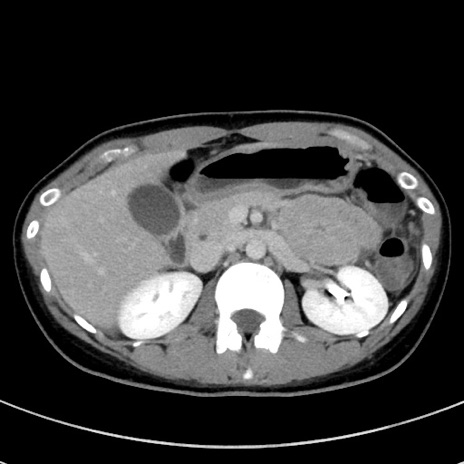

症例17(横断像)

【症例】20歳代女性

【主訴】嘔吐、下腹部痛

【現病歴】昨日夕食後に嘔吐し下腹部痛が出現。本日になっても嘔吐持続し改善しないため来院。

【身体所見】意識清明、BT 37.2℃、BP 108/67mmHg、腹部:平坦、やや硬、下腹部正中から右にかけて圧痛あり、反跳痛軽度あり、tapping pain(+)。

【データ】WBC 13600、CRP 14.94